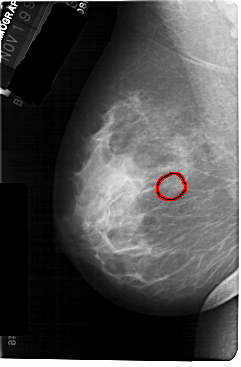

A_1301_1.LEFT_MLO

LEFT_MLO LINES 5491 PIXELS_PER_LINE 3601 BITS_PER_PIXEL 12 RESOLUTION 43.5 OVERLAY

FILE: A_1301_1.LEFT_MLO.OVERLAY

TOTAL_ABNORMALITIES 1

ABNORMALITY 1

LESION_TYPE CALCIFICATION TYPE PLEOMORPHIC DISTRIBUTION CLUSTERED

ASSESSMENT 4

SUBTLETY 2

PATHOLOGY BENIGN

TOTAL_OUTLINES 1

BOUNDARY